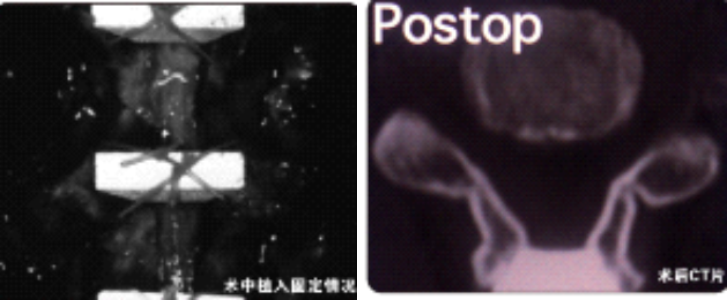

1.对脊髓后部破坏小,有效防止再关门至椎管狭窄

2.为椎管成形术提供了有效的解决方案